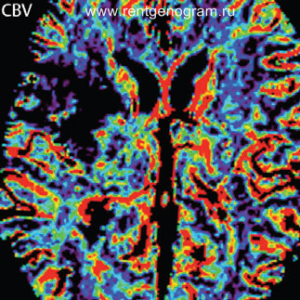

Объемы инфарктной зоны и ишемической полутени при поступлении могут служить важными предсказателями клинического исхода. Несовпадение этих объемов может помочь в отборе пациентов для внутривенного тромболитического лечения, даже если прошло более трех часов. Этот подход в сочетании с сосудистыми визуализационными методами может быть полезен для оценки возможности применения других лечебных мероприятий, таких как механическое разрушение тромба и внутриартериальный тромболизис, а также для оценки эффективности терапии.

- При совпадении показателей CBV и CBF тромболизис не требуется, вне зависимости от размеров очага.

- При наличии крупной зоны CBV и даже большей зоны CBF возможно применение тромболизиса, в зависимости от времени, прошедшего с момента инсульта и размера очага.

- Если CBV мал, а CBF велик, это создает условия для тромболизиса, но требуется осторожность, если прошло более 3 часов после инсульта.

- При CBV >100 мл тромболизис, скорее всего, не показан.